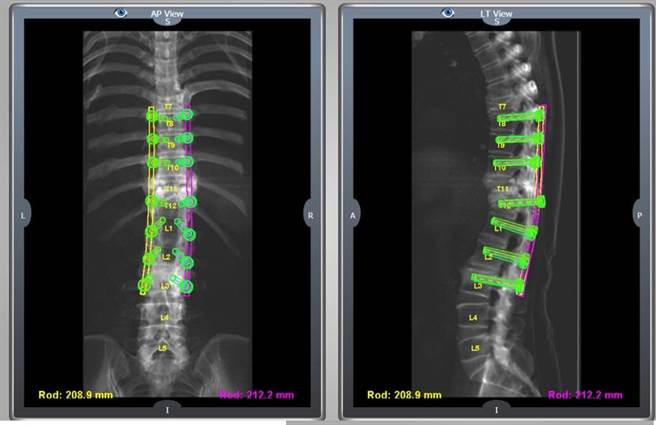

雷纳生脊椎机械手臂大幅增加钢钉植入精准度,减少神经伤害风险。(光田综合医院提供/陈淑娥台中传真)

许芳伟表示,相较于以往传统脊椎手术用人工植入钢钉,每植入一根钢钉就要照一次X光确认位置,不仅手术时间长,对神经伤害风险也相对高。在雷纳生脊椎机械手臂辅助下,使用3D电脑断层扫描,能清楚分辨骨骼、肌肉及神经组织构造,医师能在术前模拟放置角度及深度,精准快速的植入,避开神经组织,准确度高达99%,不仅能降低钢钉伤到神经的风险,也大幅缩短手术时间。